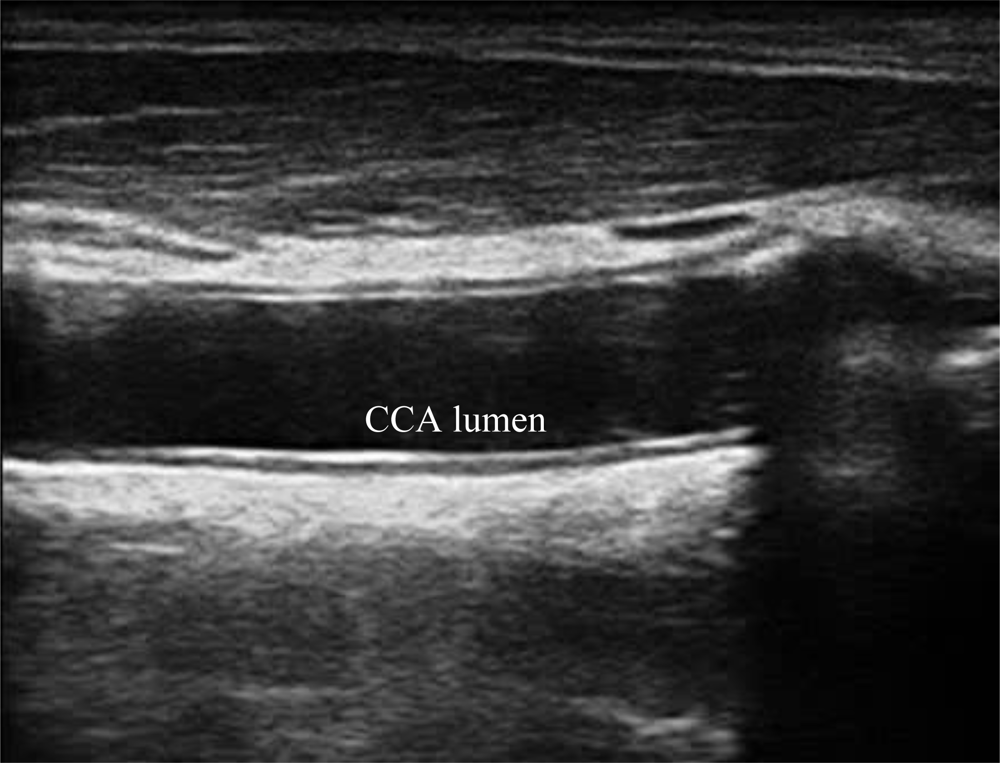

A typical B-mode image is shown in Figure 1. There are plaques on both near and far walls. On the contrary, a typical CCA image without plaque having thin and thick IMT is shown in Figures 2 and 3, respectively. Outlining the boundaries of intima and adventitia is not easy, especially on the near wall. Some features have been studied in previous studies [7,11], in which the most frequently used feature is the gradient of gray-values. From our previous studies [7,14,17], it is found that MacLeod operator combined with some specific enhancement filters are very suitable for feature extraction in intima and adventitia detections.

We have tested three image sequences: S1, S2, and S3, they include plaques, thin, and thick IMT, respectively. All sequences have at least three heart cycles. Figures 6 to 8 show the test results of IMT detection on the far wall, whereas Figures 9 to 11 show the test results of IMT detection on the near wall of the three sequences.

In Figure 6 there is a plaque on the right-hand side which is successfully detected. A total of 78 images are in sequence S1. Another example shows the ability to detect a thin IMT as shown in Figure 7. A total of 111 images are in sequence S2. Figure 8 shows the thick IMT test result. A total of 86 images are in sequence S3.